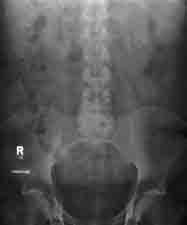

| Obstipation mit Kolontransitzeitbestimmung | Darmverschluss | Freie Luft in Linksseitenlage |

, in der Erkennung von chronischen (z.B. Abb. Links: Obstipation mit Kolontransit-Zeitbestimmung nach oraler Einnahme röntgendichter Marker) und akuten Erkrankungen des Bauches bzw. Abdomens (z.B. Abb. Mitte: Darmverschluss=Ileus. Abb. Rechts: Freie Luft in Linksseitenlage bei Hohlorganperforation,

| Abdomenleeraufnahme | 10 Minuten post-KM | 20 Minuten post-KM |

Abb. Links: Abdomenleeraufnahme im Liegen, Abb. Mitte: Regelrechte Exkretionsphase 10 Minuten post-KM) und in der Erfassung von pathologischen Befunden in der Ausscheidungsurographie (z.B.. Abb. Rechts: Regelrechte Darstellung von Ureteren und Nieren 20 Minuten post-KM. Harnblasendivertikel bei Balkenblase infolge einer benignen Prostatahyperplasie).